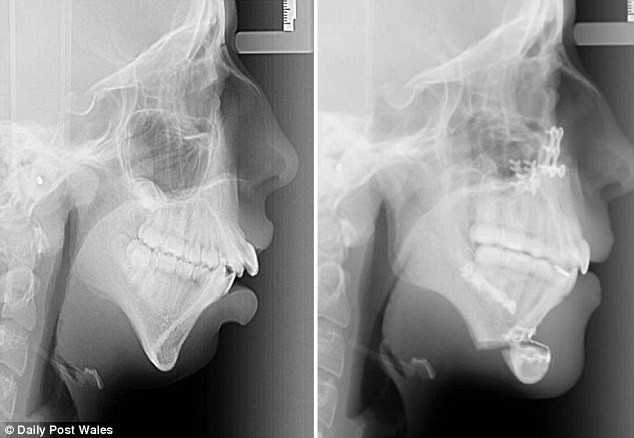

Cô gái trẻ lột xác hoàn toàn sau nhiều lần phẫu thuật đau đớn ảnh 1Ellie Jones trước và sau khi trải qua phẫu thuật. (Nguồn: dailymail.co.uk)

Năm 8 tuổi, xương hàm của Ellie Jones ngừng phát triển. Điều đó khiến hàm răng của cô mọc lộn xộn.

Năm 14 tuổi, Ellie Jones bắt đầu niềng răng và sau đó bác sỹ phát hiện xương hàm của cô không phát triển từ năm lên 8.

Năm 16 tuổi, Ellie Jones trải qua cuộc phẫu thuật đầu tiên. Cô nói: "Trong thời gian đó, tôi chỉ được ăn thức ăn loãng và không thể nói chuyện bình thường. Tôi phải viết lên giấy nếu muốn nói chuyện với người khác."

Trong một năm sau đó, các bác sỹ đã phải hội chẩn rất nhiều lần về ca phẫu thuật hàm dưới cho Ellie Jones. Cuối cùng, họ quyết định sẽ cấy ghép xương cằm mới.